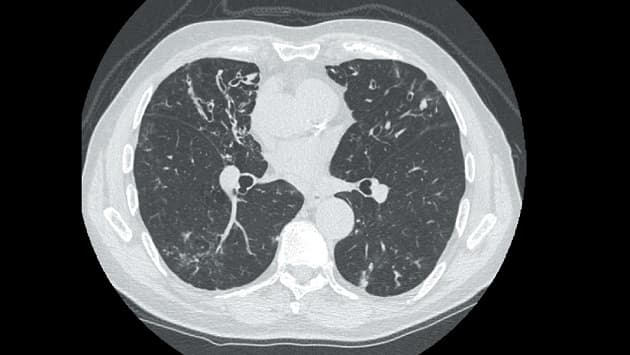

© Højresolutions-CT-billede af bronkiektasier.

Modsat astma og KOL er bronkiektasier en kronisk lungesygdom, hvor forskningsinteressen hidtil har været relativt begrænset. Imidlertid har øget anvendelse af højresolutions-CT ved udredning af lungepatienter vist en højere prævalens end tidligere antaget, hvilket har øget forskningsinteressen. Statusartiklen af Hilberg et al gennemgår forekomst, ætiologi og diagnostik og foreslår en individualiseret behandling afhængig af fænotypen og endotypen.